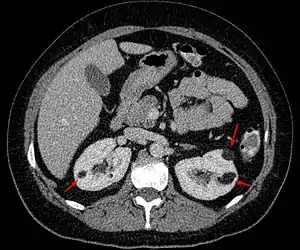

| Angiomyolipoma in both kidneys (arrows) in computer tomography. The tumours are hypodense (dark) due to fat content | |

Three methods of scanning can detect Angiomyolipomas: ultrasound, computed tomography (CT), and magnetic resonance imaging (MRI).[5] Ultrasound is standard and is particularly sensitive to the fat in Angiomyolipomas, but less so to the solid components. However, accurate measurements are hard to make with ultrasound, particularly if the Angiomyolipoma is near the surface of the kidney (grade III).[4] CT is very detailed and fast, and allows accurate measurement. However, it exposes the patient to radiation and the dangers that a contrast dye used to aid the scanning may itself harm the kidneys. MRI is safer than CT, but many patients (particularly those with the learning difficulties or behavioural problems found in tuberous sclerosis) require sedation or general anaesthesia, and the scan cannot be performed quickly.[3] Some other kidney tumours contain fat, so the presence of fat is not diagnostic. Distinguishing a fat-poor angiomyolipoma from a renal cell carcinoma (RCC) can be difficult.[6] Both minimal fat AMLs and 80% of the clear-cell type of RCCs display signal drop on an out-of-phase MRI sequence compared to in-phase.[7] Thus, a lesion growing at greater than 5 mm per year may warrant a biopsy for diagnosis.[3]